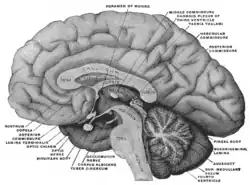

Mesal aspect of a brain sectioned in the median sagittal plane.